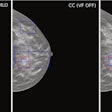

- Lunit Insight MMG: Mammography analysis solution

- Lunit Insight DBT: Digital breast tomosynthesis interpretation

The first commercial deployments are already underway, the firm added, including the use of Insight MMG at Radiologische Allianz in Hamburg, supporting the Hamburg breast cancer screening program under the Starvision network.

Together with deployments at Die Radiologie, a major regional hospital group operating over 20 medical sites across Bavaria, Lunit's software now supports approximately 120,000 breast cancer screenings and diagnoses annually across the two institutions, the company said.